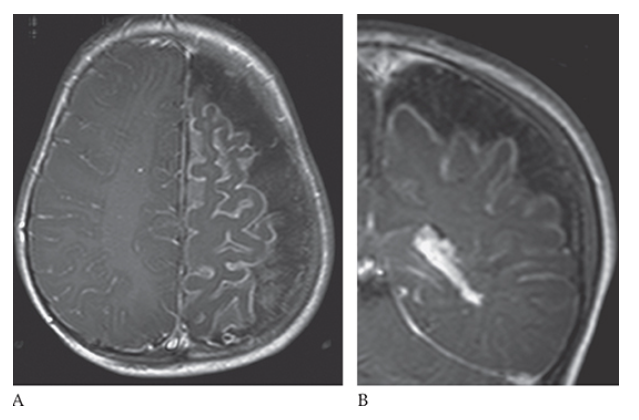

What is A

Meningioma. T1-weighted axial MR image shows an isointense left parasagittal meningioma and postcontrast T1-weighted images in the axial

What is B

Meningioma. T1-weighted axial MR image shows an isointense left parasagittal meningioma coronal

What is C

Meningioma. T1-weighted axial MR image shows an isointense left parasagittal meningioma and sagittal

What is D

Meningioma. T1-weighted axial MR image shows an isointense left parasagittal meningioma planes.